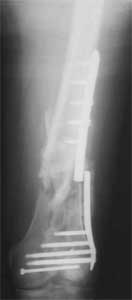

Отправитель: Enes M. Kanlic 13 Ноябрь 2004, 19:43

Attached are few examples from our Hospital:

A. Difficult reductions, even in retrograde nailing (my preference, easier control of "small" distal fragment) and it is much, much harder to do it anterograde (Alex, do you have one good case in your collection of anterograde nailing in very distal fractures - as you have suggested that I

should have done it in my previously posted case?

Malpositioning is much too common (recurvatum, varus - valgus).

B. Fixation loosening: distal cutting of the nail, non-unions do happen (cases attached).

Locking Plating has more distal screws than any nail, fixed angles and provides much better fixation, especially in osteoporotic bone.